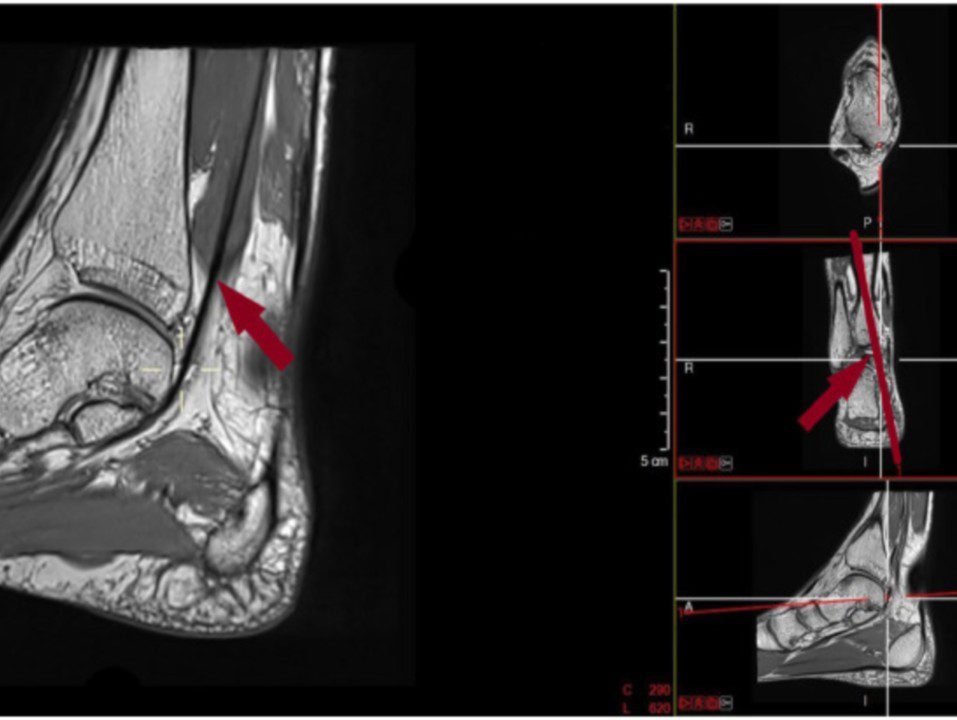

Doctors Nils Reymond, Victor Dubois-Ferrière, and Mathieu Assal have published a scientific work on functional hallux limitus. The question addressed is whether patients with this condition have a thin or fleshy muscle body.

│Abstract│ Background: Functional hallux limitus (FHLim) refers to a limitation of hallux dorsiflexion when the first metatarsal head is under load, whereas physiologic dorsiflexion is measured in the unloaded condition. Limited excursion of the flexor hallucis longus (FHL) in the retrotalar pulley has been identified as a possible cause of FHLim. A low-lying or bulky […]